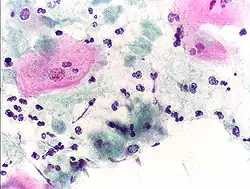

- Micrograph of a Pap test showing trichomoniasis. Trichomonas organism seen in the upper right. Pap stain.